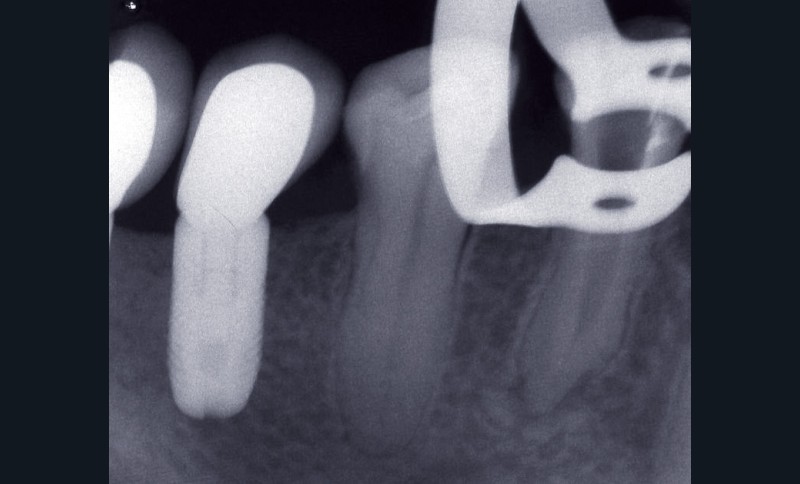

La troisième éventualité concerne le dépassement de matériau d’obturation canalaire (fig. 5) ou d’autres corps étrangers provoquant une réaction immunogène.

La présence d’éléments étrangers piégés dans le périapex au cours du traitement endodontique peut entretenir la lésion alors appelée granulome à corps étranger. Ainsi, même biocompatibles, des matériaux comme la gutta percha peuvent retarder la cicatrisation apicale [16], et ce d’autant si le cône de gutta percha ne présente pas toutes les garanties d’asepsie préalable ou s’il est contaminé par la présence de talc ou de poudre de latex provenant des gants. Sjögren et coll. [38] décrivent deux cas de figure. Si les éléments extrudés de gutta percha sont volumineux, ils seront encapsulés par une membrane collagénique. A contrario, si les particules sont fines, situation plus défavorable, elles induisent une réponse localisée intense, caractérisée par la présence de macrophages et de cellules géantes multinucléées à l’origine même de l’initiation de la lésion apicale. D’autres éléments néfastes à la guérison apicale peuvent être retrouvés. Ainsi, des particules végétales d’origine alimentaire peuvent être introduites dans le système endocanalaire si celui-ci est en contact avec la cavité buccale comme cela peut être le cas lors d’un traumatisme important ou d’une dent laissée ouverte. D’autres éléments extrinsèques peuvent être importés au cours de la préparation ou de l’obturation canalaire, comme des particules d’amalgame, de résine composite ou d’obturation temporaire. D’autres particules, par exemple les fibres de cellulose piégées lors du séchage canalaire à l’aide de pointes de papier ou issues des cotons éventuellement employés en interséance, peuvent contrarier la cicatrisation. Ces éléments sont en effet difficilement dégradés par les cellules de défense de l’hôte et peuvent même favoriser la croissance de biofilms bactériens à leur surface.

S’il est admis aujourd’hui qu’il est préférable de traiter endodontiquement les dents exemptes de lésions apicales en une seule séance [8], la question reste posée pour les dents affectées d’une LIPOE. Faut-il procéder de façon systématique à une phase de médication temporaire au cours du traitement endodontique des dents porteuses d’une lésion péri-apicale ? Certains auteurs [1, 35, 39] préconisent la mise en place d’une phase d’hydroxyde de calcium (CaOH2) afin d’obtenir un canal exempt de bactéries. À l’inverse, d’autres études [7, 24, 25, 40, 46] s’accordent sur le fait qu’il n’y a pas de différence significative entre le traitement en une ou plusieurs séances des dents porteuses d’une PAC, en termes tant de taux de guérison que de complications postopératoires (fig. 6).